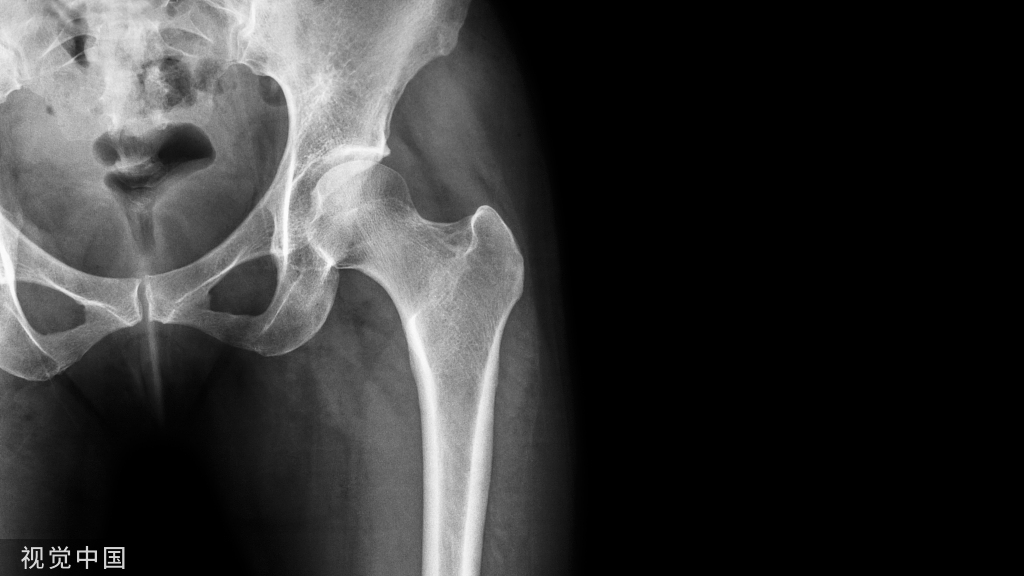

(六)、股骨髓针手术的体位

- 患者向健侧半侧卧位头下置头圈,垫高髋部和背部15°~30°。

- 健侧上肢用术臂带固定于搁手架上,患侧上肢用软垫包裹置于胸前。

- 健侧下肢屈曲,在膝下及踝关节部置一方垫,膝部放一海绵垫约束带固定。